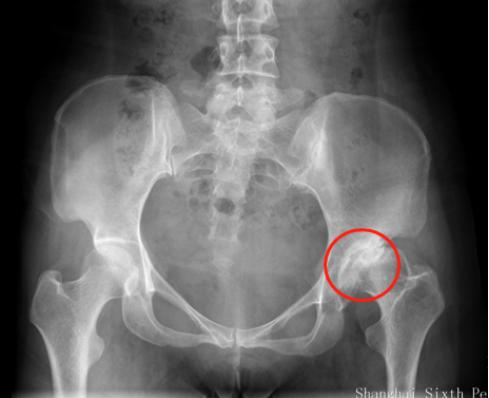

刘万军主任在听取了杨女士的病情描述后,细心安排其做了各项检查,经过检查,左髋臼发育浅,股骨头变扁,密度不均匀,关节面毛糙,关节间隙狭窄,髋臼上缘边缘硬化,关节半脱位。 诊断为:左髋关节发育不良,轻度扁平髋,继发骨性关节炎,关节半脱位。

对于刚出生的婴幼儿,可通过超声检查筛查髋关节发育不良,而对于成人髋关节发育不良患者来说,临床上最常用的为X线检查,主要表现为髋臼发育浅小,股骨头的负重侧间隙变窄等,必要时进行 CT和MRI检查。